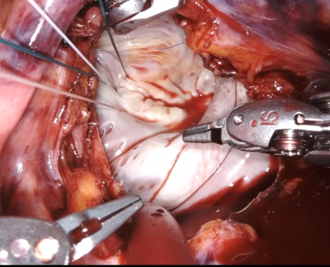

ロボット支援下で行う僧帽弁形成術のカメラ画像